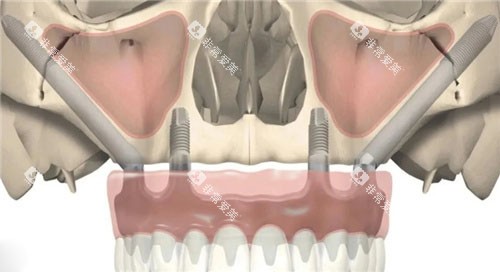

1.穿颧种植示意图

位置:种植体从牙槽嵴顶斜向上方,穿过上颌窦后壁,进入颧骨内侧壁。

手术步骤:

切开牙龈,暴露上颌骨侧壁和颧骨区域。

使用特殊钻针在颧骨上制备种植窝洞。

植入长度为18-20mm的种植体,确保与颧骨形成骨性结合。